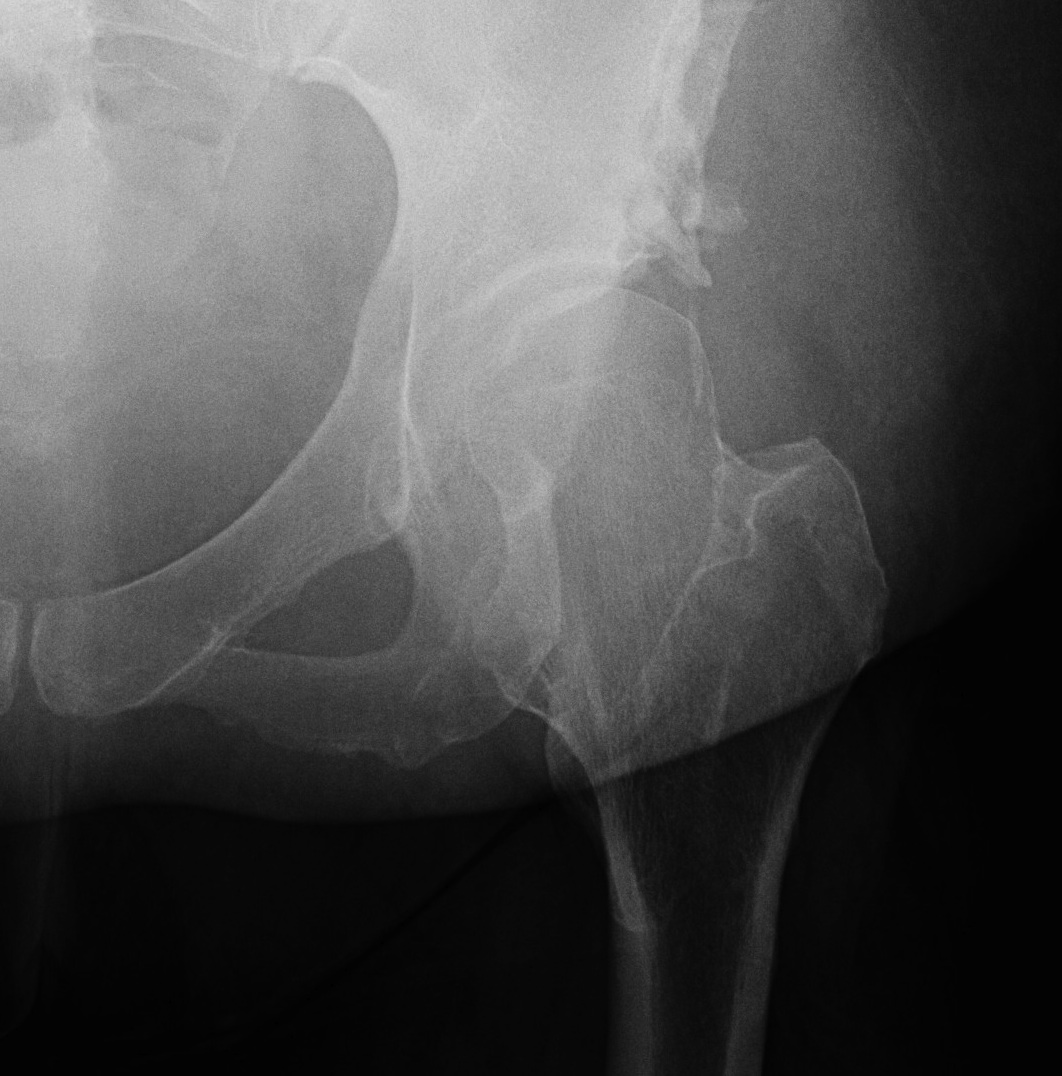

10. Chiari

Concept

- medial displacement to develop shelf

- cartilage interposed to develop fibrocartilage

Results

Luiket al JBJS 1991

- 82 of Chiari's original patients

- 20 required THR

- 75% good

- best results: 80% coverage, < 45 years, high osteotomy slope, adequate medialisation

Reynolds JBJS 1986

- 90% success at 5 years

Pitfalls

1. Distal fragment must go medially & adducted

2. Must angle osteotomy anterolaterally distally to posteromedial proximally

3. Anterior defect needs bone grafting